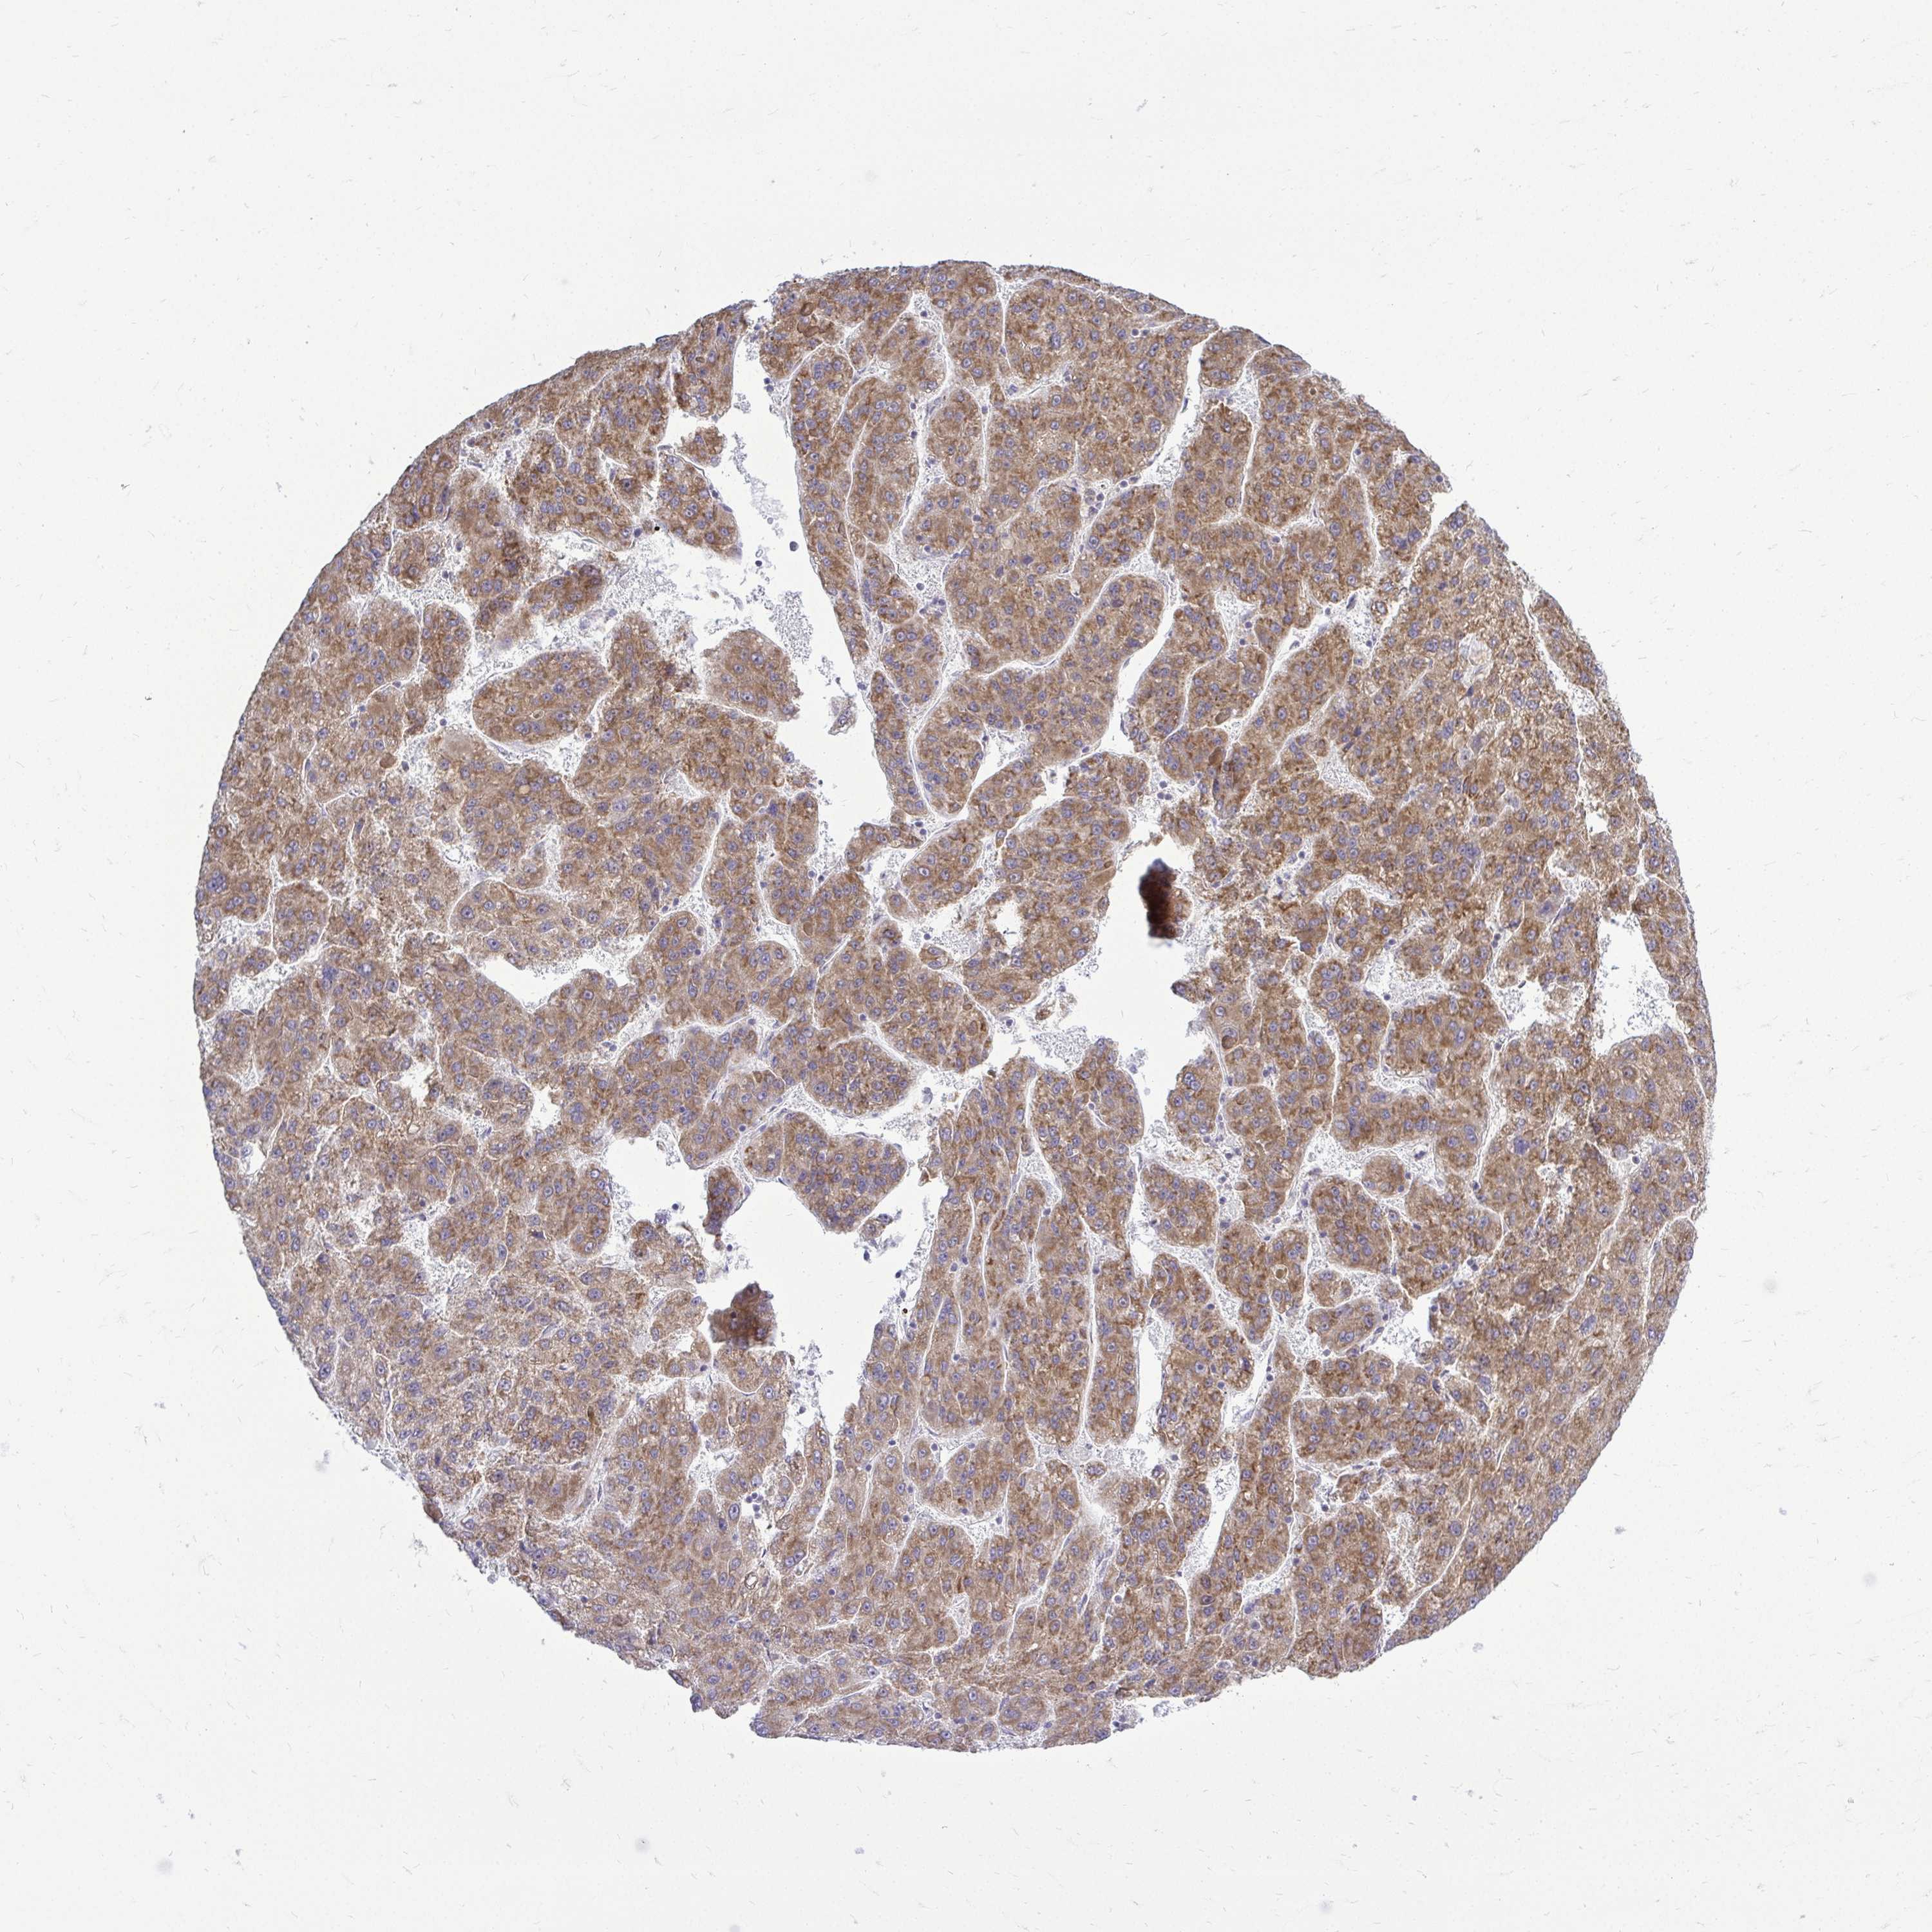

LIVER CANCER - Protein expressioni

A mouse-over function shows sample information and annotation data. Click on an image to view it in a full screen mode. Samples can be filtered based on level of antibody staining by selecting one or several of the following categories: high, medium, low and not detected. The assay and annotation is described here.

Note that samples used for immunohistochemistry by the Human Protein Atlas do not correspond to samples in the TCGA dataset.

Antibody stainingi

Antibody staining in the annotated cell types in the current human tissue is reported as not detected, low, medium, or high, based on conventional immunohistochemistry profiling in selected tissues. This score is based on the combination of the staining intensity and fraction of stained cells.

Each image is clickable and will lead to virtual microscopy that enables deeper exploration of all samples and also displays staining intensity scores, fraction scores and subcellular localization as well as patient and tissue information for each sample.

Antibody HPA050118

Antibody HPA056084

Antibody CAB012444

Staining

High

Medium

Low

Not detected

Intensity

Strong

Moderate

Weak

Negative

Quantity

>75%

75%-25%

<25%

None

Location

Nuclear

Cytoplasmic/membranous

Cytoplasmic/membranous,nuclear

Carcinoma, Hepatocellular, NOS

Cholangiocarcinoma